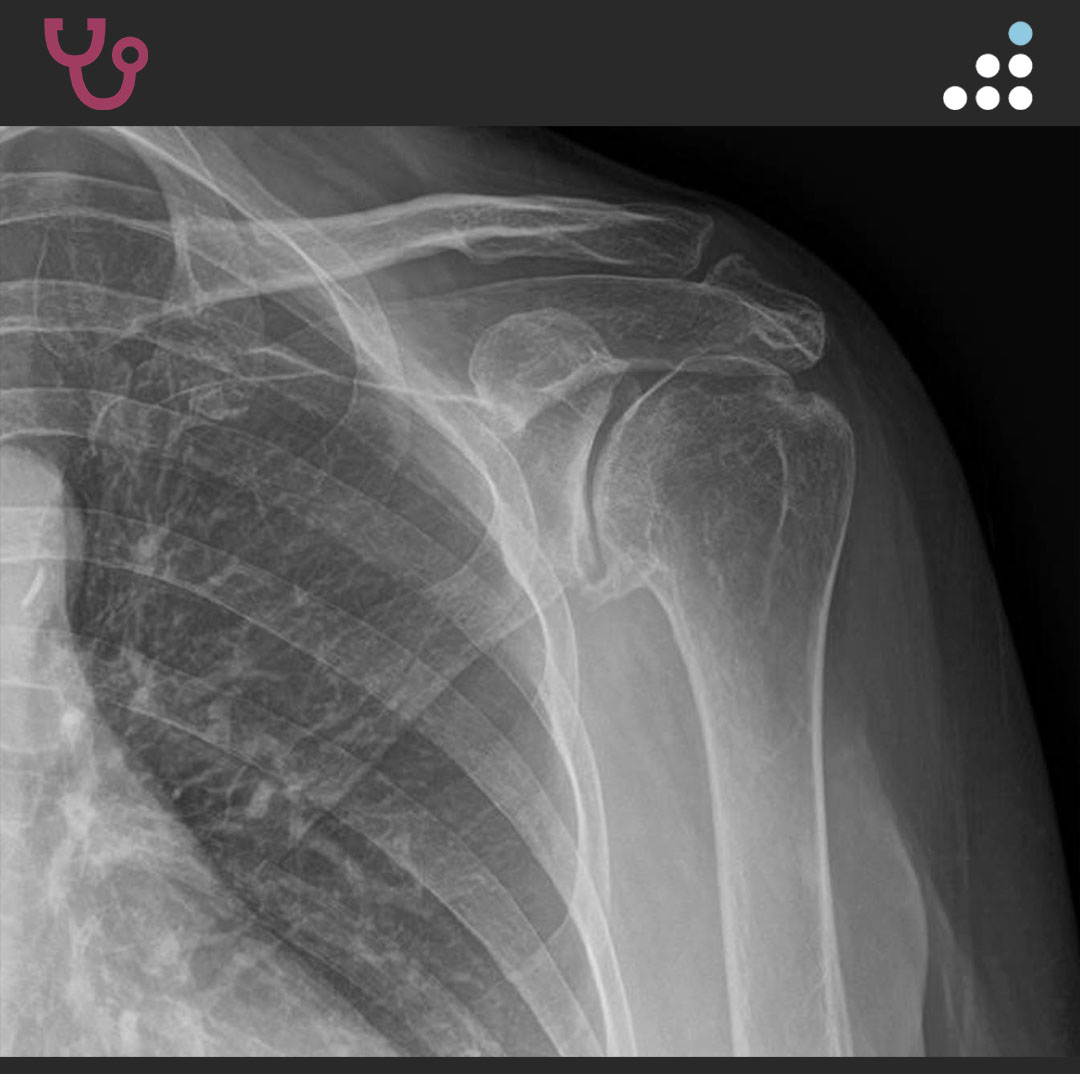

@orthobullets If there is still some cartilage left on the reverse Hill Sachs I’ve had some luck with doing a humeral head osteoplasty. I’ll use allograft chips or cement to backfill the defect after I tamp up articular surface and then try to get everything repaired especially in young pts